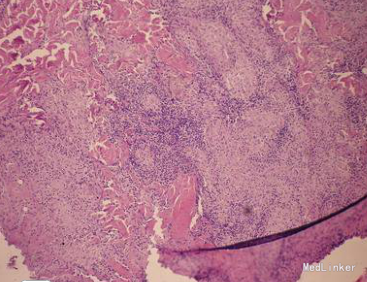

查体:一般情况良好,生命体征正常,全身浅表淋巴结未触及肿大,心肺及腹部检查无异常。皮肤科检查:右耳切除处见红褐色浸润性斑块,触之柔软,界限清楚,融合成大瘢痕。实验室检查:血常规、尿常规、肝肾功能均正常,胸部X线检查无异常;结核菌素试验强阳性(硬结直径超过20 mm)。血红细胞沉降率升高。皮损真菌培养阴性,快速血浆反应环状卡片试验(RPR)及梅毒螺旋体血凝试验(TPHA)均为阴性。皮损病理检查显示:表皮棘层肥厚,角化过度乳头瘤样增生,真皮浅层弥漫性淋巴细胞、中性粒细胞浸润。其中可见结节样的上皮样细胞和多核巨细胞,中央可见干酪样坏死。皮损分泌物通过分枝杆菌培养4周阳性,菌型鉴定为结核分枝杆菌。

皮肤结核是结核分枝杆菌侵犯皮肤或其他脏器,结核病灶累及皮肤引起的皮肤损害,可迁延数年或数十年之久。如果治疗不及时,可能留下损毁性瘢痕。寻常狼疮是一种慢性进行性皮肤结核病,病程可长达数十年。病损常缓慢扩大,可波及大片皮肤,损坏鼻、耳、口唇、眼睑等处,形成瘢痕甚至毁容等。患者的皮损表现为孤立浸润性斑块及结节,结合皮损组织病理检查可确诊为皮肤结核(寻常狼疮)。

学习了,干酪样坏死,多核巨细胞,结核结节啊。不知道此患者的寻常狼疮跟右耳切除有没有关系。